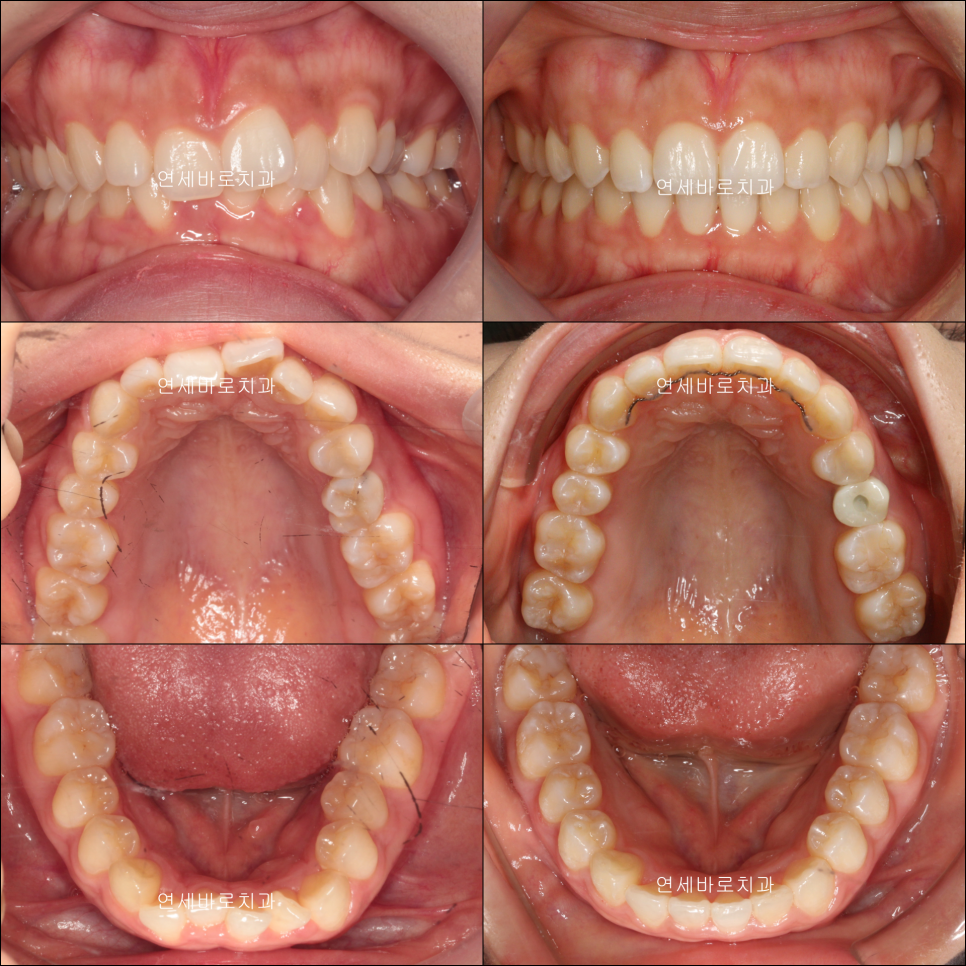

재제작 결정되던 시기의 모습입니다.

22년 7월 치료가 마무리 되었습니다.

재제작을 준비하는 과정에서 임플란트 수술을 진행하였고, 교정이 마무리되는 7월에 함께 마무리할 수 있게 해드렸습니다.

이게 교정과 임플란트 둘다 진행하는 치과에서 누릴 수 있는 장점입니다.

치료 전 후의 모습입니다.